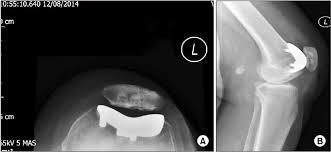

La Prótesis Femoropatelar de Rodilla.

La prótesis parcial femoropatelar de la rodilla es una prótesis especial que está indicado en pacientes con un desgaste muy inicial y con un patrón que afecta solo el compartimiento anterior de la rodilla. Típicamente, son pacientes con dolor en la parte de delante de la rodilla al estar sentados o al subir o bajar escaleras. No les molesta al caminar sobre un terreno plano sin desnivel. Tiene la ventaja de resecar mucho menos hueso del paciente, así preservando más hueso para el futuro. Además, al mantener la parte biológica del cartílago y la ligamentosa de los cruzados de la rodilla, parece conservar mucho mejor la sensibilidad y la marcha de la rodilla (la propiocepción). También la recuperación de esta cirugía (al ser menos agresiva) es más rápida.

|

|

Los mejores resultados de supervivencia se ven en pacientes con poca enfermedad y poca deformidad del aparato extensor, mayor de edad o con normo/bajo peso. Los pacientes candidatos a esta protesis probablemente no son más de 2-3 % del total de pacientes con artrosis de la rodilla. Además, su uso es restringido debido a la probabilidad de la progresión de a enfermedad dentro del resto de la articulación, que puede ser generador del dolor y fracaso de la prótesis con el paso de los años. Por tanto, cuando se decide por optar por este implante precisa un consenso claro entre el cirujano y el paciente entendiendo todos los variables que puedan surgir. Siempre que se plantea colocar una protesis femoropatelar habitualmente también se tiene preparado la protesis total por si el grado de enfermedad comprobado durante la cirugía es más de la prevista antes de la cirugía.